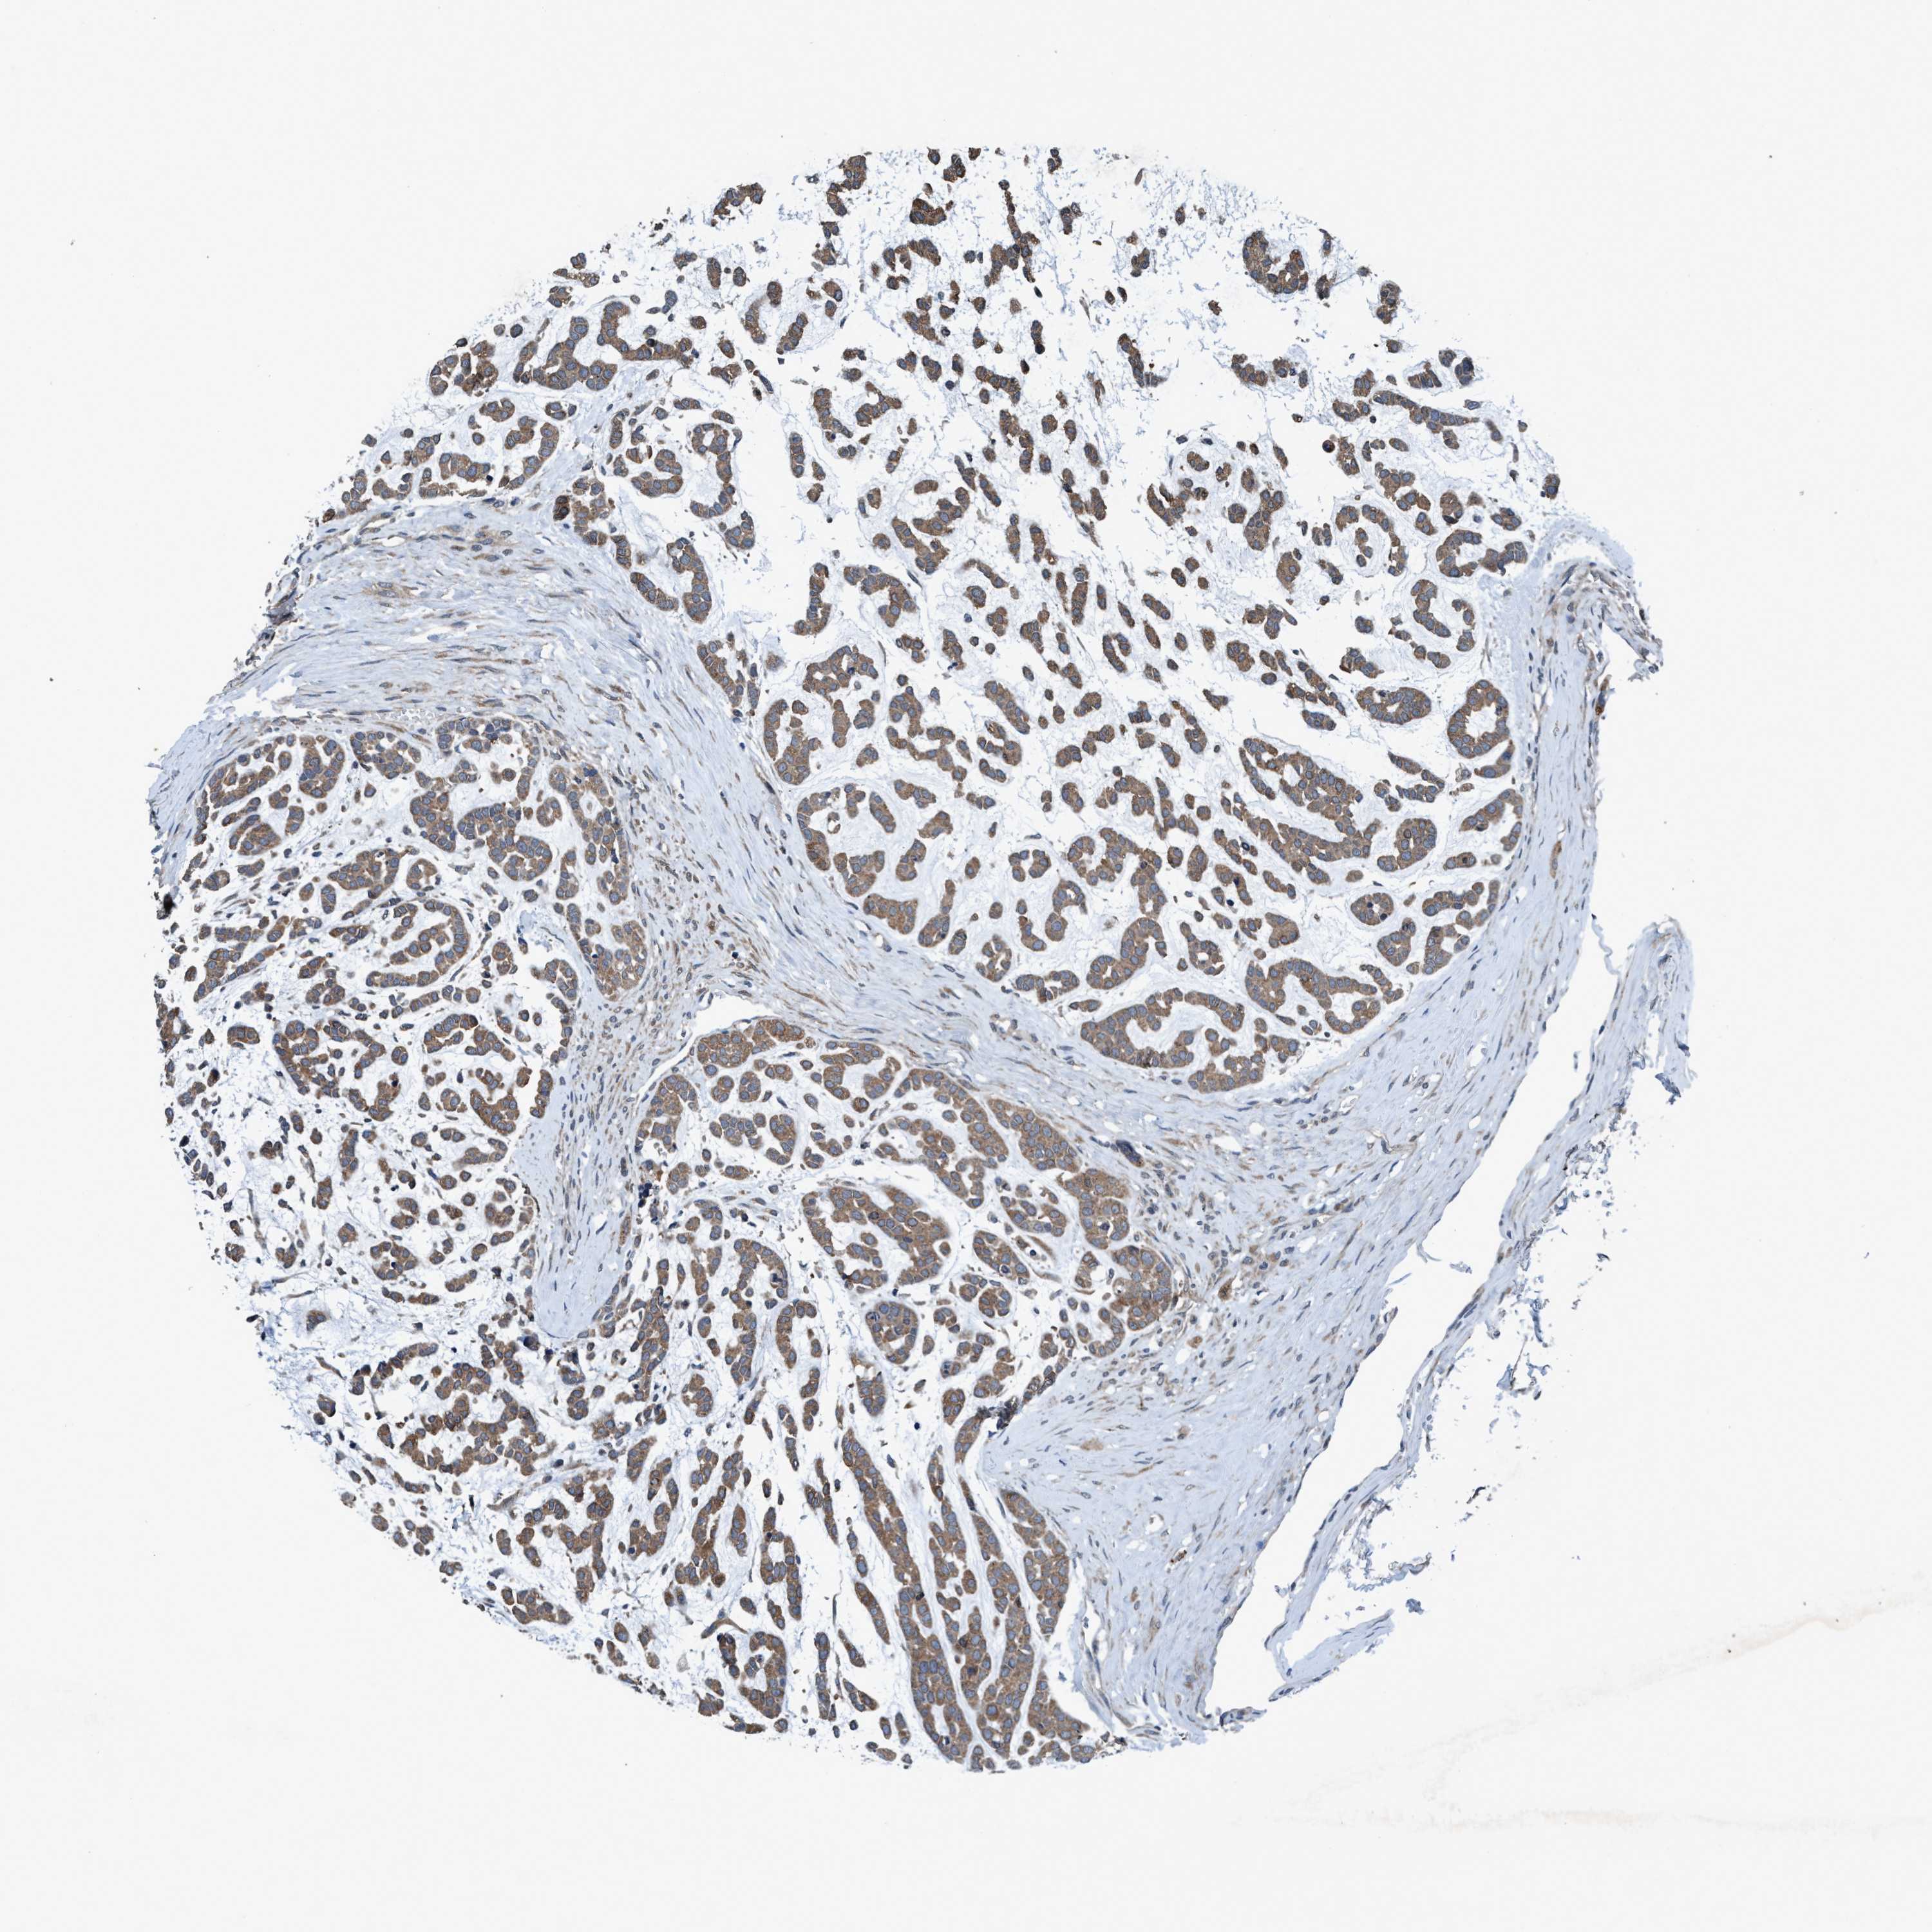

HEAD AND NECK CANCER - Protein expressioni

A mouse-over function shows sample information and annotation data. Click on an image to view it in a full screen mode. Samples can be filtered based on level of antibody staining by selecting one or several of the following categories: high, medium, low and not detected. The assay and annotation is described here.

Antibody stainingi

Antibody staining in the annotated cell types in the current human tissue is reported as not detected, low, medium, or high, based on conventional immunohistochemistry profiling in selected tissues. This score is based on the combination of the staining intensity and fraction of stained cells.

Each image is clickable and will lead to virtual microscopy that enables deeper exploration of all samples and also displays staining intensity scores, fraction scores and subcellular localization as well as patient and tissue information for each sample.

Antibody HPA064427

Antibody CAB021903

Staining

High

Medium

Low

Not detected

Intensity

Strong

Moderate

Weak

Negative

Quantity

>75%

75%-25%

<25%

None

Location

Nuclear

Cytoplasmic/membranous

Cytoplasmic/membranous,nuclear

Squamous cell carcinoma, NOS

Adenocarcinoma, NOS

Squamous cell carcinoma, metastatic, NOS

Adenoma, NOS